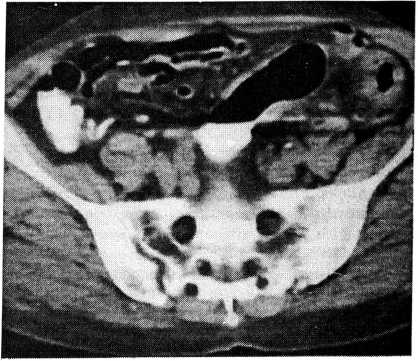

Рис. 1. Томограмма при язвенном колите, осложненном токсической дилатацией. Выявляются увеличение диаметра толстой кишки, утолщение и двойной контур кишечной стенки.

При патологическом сужении диаметра поперечного сечения левого фланга толстой кишки у 8 больных наблюдалось компенсаторное расширение диаметра поперечного сечения правого фланга. У 4 больных с тяжелой формой язвенного колита и признаками токсической дилатации выявлялся двойной контур кишечной стенки (рис. 1), что было связано, по-видимому, со значительным отеком слизистой оболочки и десквамацией эпителия, при этом площадь просвета кишечника значительно увеличивалась. У 3 больных РКТВК позволила обнаружить в просвете кишечника полипообразные разрастания в виде спикул (псевдополипы). У одного больного была определена не выявленная ранее при ирригоскопии и колоноскопии опухоль поперечной ободочной кишки, имевшая инфильтративный рост. Диагноз аденокарциномы подтвердился при оперативном лечении и гистологическом исследовании.